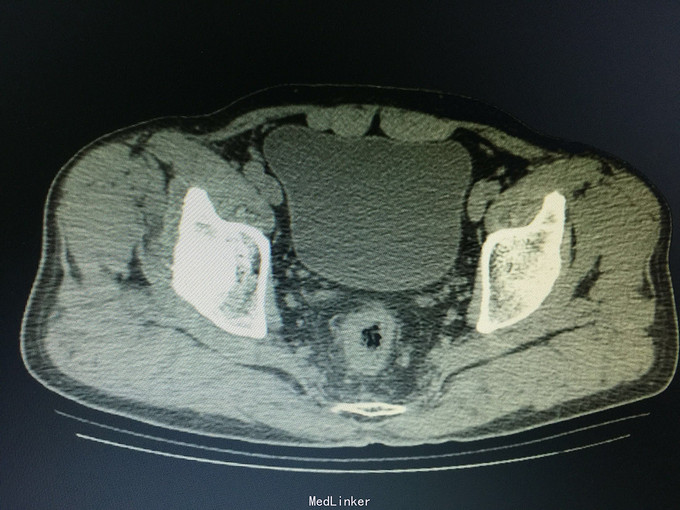

一般状态好,无贫血貌,肛门外缘不规整,肛门指诊:距肛缘4cm可及溃疡性肿物,近环形,固定,指套染陈旧血。 辅助检查:盆腔CT:直肠管壁不规则肥厚,官腔偏心性狭窄,周围见条索影及结节影。

诊断:直肠癌, 预约结肠镜检查:距肛缘4cm见环肠肿物,凸凹不平,表面覆污秽苔,质硬,界不清。 病理结果为直肠腺癌。 病人回当地医院接受治疗。